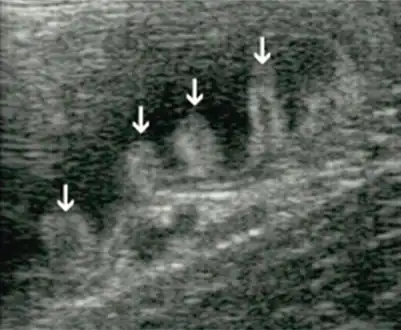

- Bacterial overgrowth syndrome arrow

- Aspiration of bacteria from the jejunum is the gold standard for diagnosis. A bacterial load of greater than 105 bacteria per millilitre is diagnostic for bacterial overgrowth

- Biopsies of the small bowel in bacterial overgrowth can mimic celiac disease, with partial villous atrophy.